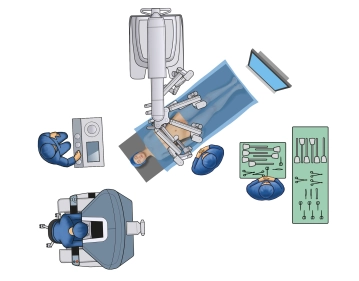

- Recomenda-se posicionar ambos os braços (cuidado: envoltório de algodão ao posicionar com uma tipoia de pano), ou posicionar um braço ao lado do robô

- Para o posicionamento das pernas, recomenda-se "botas" acolchoadas para que as pernas possam ser movidas separadamente e cobertas de forma estéril, se necessário. Alternativamente, as pernas podem ser posicionadas em suportes de pernas com fixação (Cuidado: Síndrome compartimental).

- As pernas devem ser ajustáveis via controle da mesa cirúrgica durante o procedimento